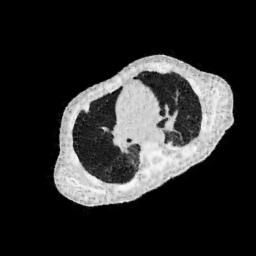

4.4 Limited-Angle CT Reconstruction

To test the proposed framework’s performance on limited-angle reconstruction, we redo the experiment in the above section with the angular range changing from to for parallel-beam geometry and to for fan-beam geometry, one projection per degree. The experiment results are shown in Fig.6. Also, the ground truth and the limited-angle CT reconstruction results of different methods are shown in the row of Fig.7 (parallel-beam, LIDC-IDRI dataset), and Fig.8 (fan-beam, LIDC-IDRI dataset).

(a) Ground Truth

30.15dB

(b) ASD-POCS

39.35dB

(c) RBP-DIP

27.10dB

(d) DIP

23.88dB

(e) MED50

20.59dB

(f) RED-CNN